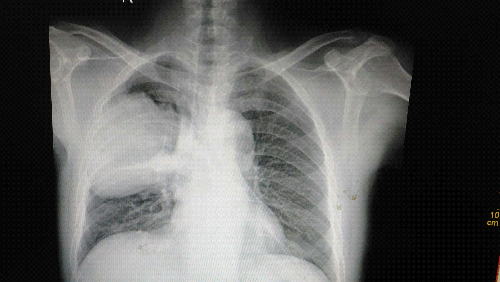

X13823:男,63,神内科病人,肺内占位?

常规检查发现,没做CT

右俩中下叶偏后见臣大肿块,边缘较光整浅分叶,右侧叶间裂增厚,考虑:右位点位,肺癌可能性大,右侧胸膜叶间裂积液。

右肺中叶见肿块影、有毛刺、叶间裂增宽、考虑占位、建议CT

右肺上叶后段团块状软组织密度影,边缘清楚并见分叶,下缘以叶间裂为界,右肺水平裂增宽、密度增高均匀,余肺野未见实质性病变,心影形态大小未见明显异常,两侧膈面光滑,肋膈角锐利。老年男性患者,考虑右肺上叶占位性病变,肺癌可能性大,右肺叶间积液。建议CT检查。

右肺中下叶偏后可见巨大肿块,浅分叶,右侧叶间裂积液,考虑右肺巨大占位------肺癌侵犯胸膜?不排除肺肉瘤,建议CT检查。

首先这是肺内团块状影,老年人,还是考虑肺内占位性病变。

张力性占位,边缘光,提示囊性病变或包裹性积液。